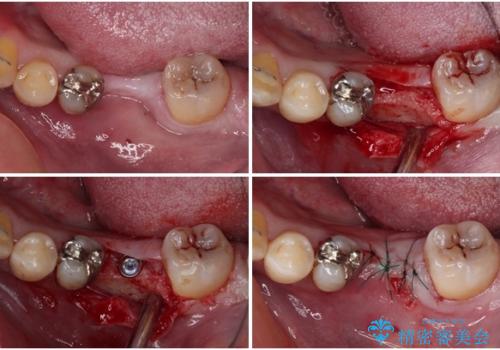

左右下顎の大臼歯は、ともに歯根が破折しており、抜歯が必要な状態でした。

放置したことで炎症による骨吸収が顕著であるため、骨造成を併用してインプラント埋入を行うこととしました。

矯正治療でインプラント埋入を行い、矯正治療後に気になる前歯と合わせてオールセラミッククラウンによる補綴治療を行うこととしました。